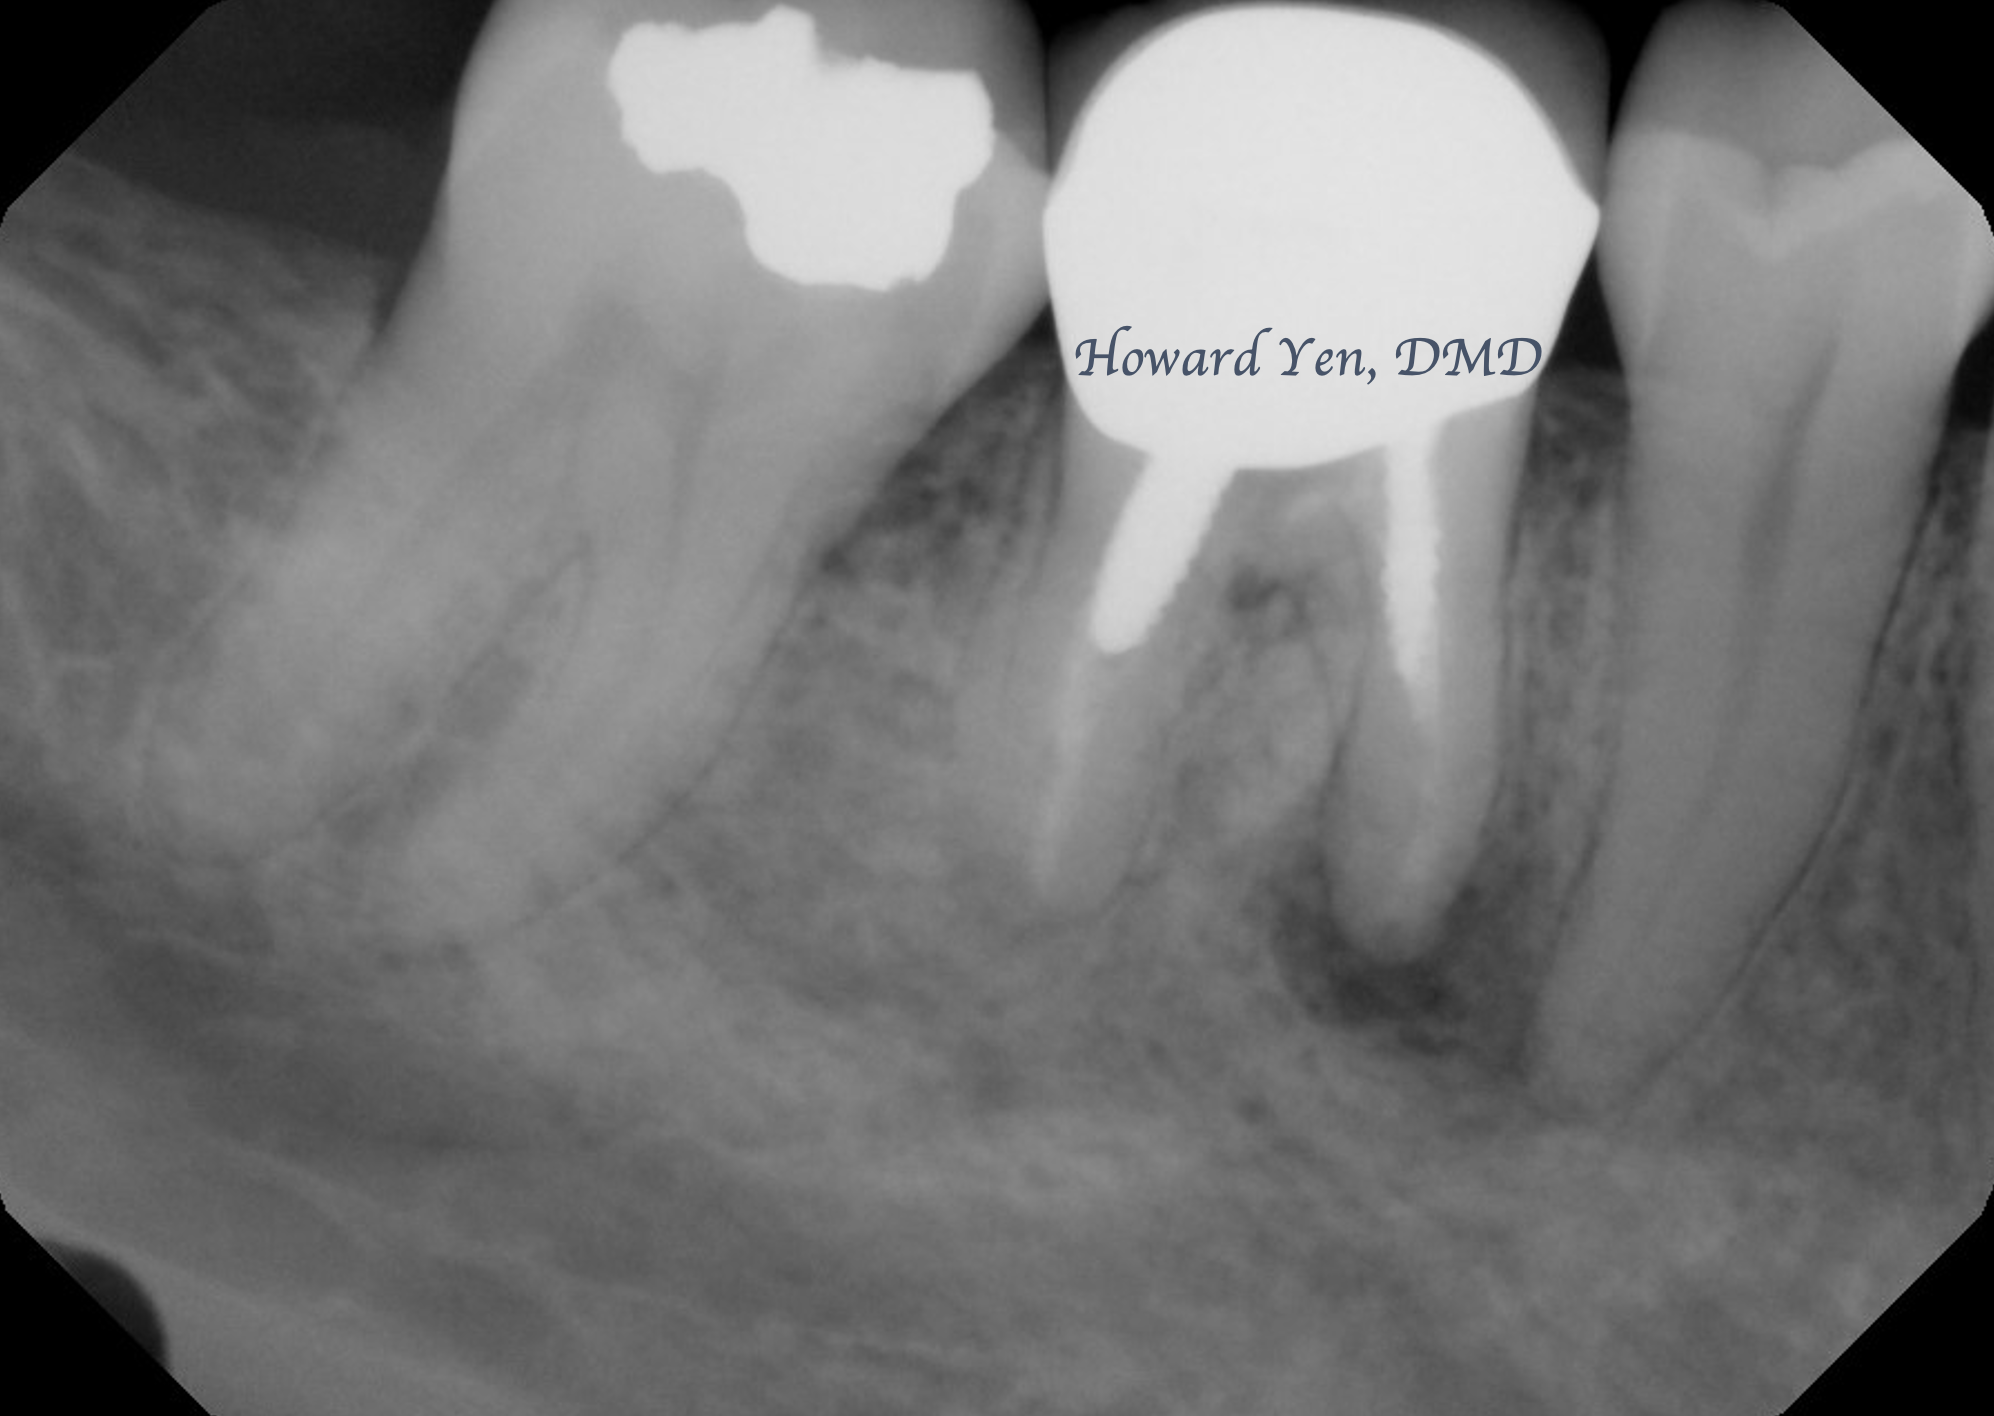

Root Amputation

Root amputation is a surgical procedure to remove diseased/fractured root of a molar in an attempt to further salvage the tooth (crown). The procedure is often done in collaboration with Endodontist (Root Canal Specialist). This is one of the classic conservative treatment option prior to the advent of modern dental implants. With proper case selection, this treatment modality is still an excellent option in preserving natural tooth.